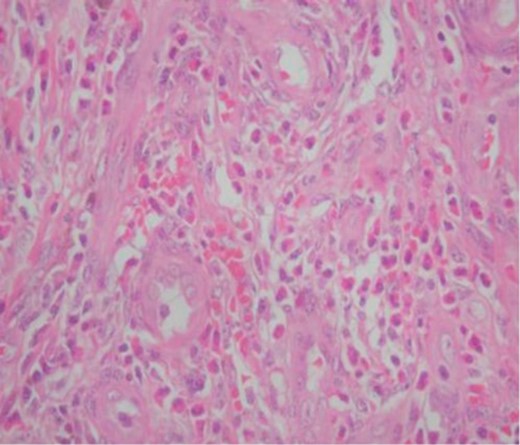

Postoperative recovery was excellent, and the patient was discharged on the second postoperative day. Histological examination revealed proliferation of small blood vessels lined with plump endothelial cells and surrounded by a lymphoid infiltrate with formation of germinal centers. Large numbers of eosinophils were observed (Fig. 2). A diagnosis of ALHE was made. No recurrence was found after a follow-up period of 9 months (Fig. 3).

Histopathological picture of the lesion showing plump endothelial cells and surrounded by a lymphoid infiltrate with formation of germinal centers. Large numbers of eosinophils are also seen.